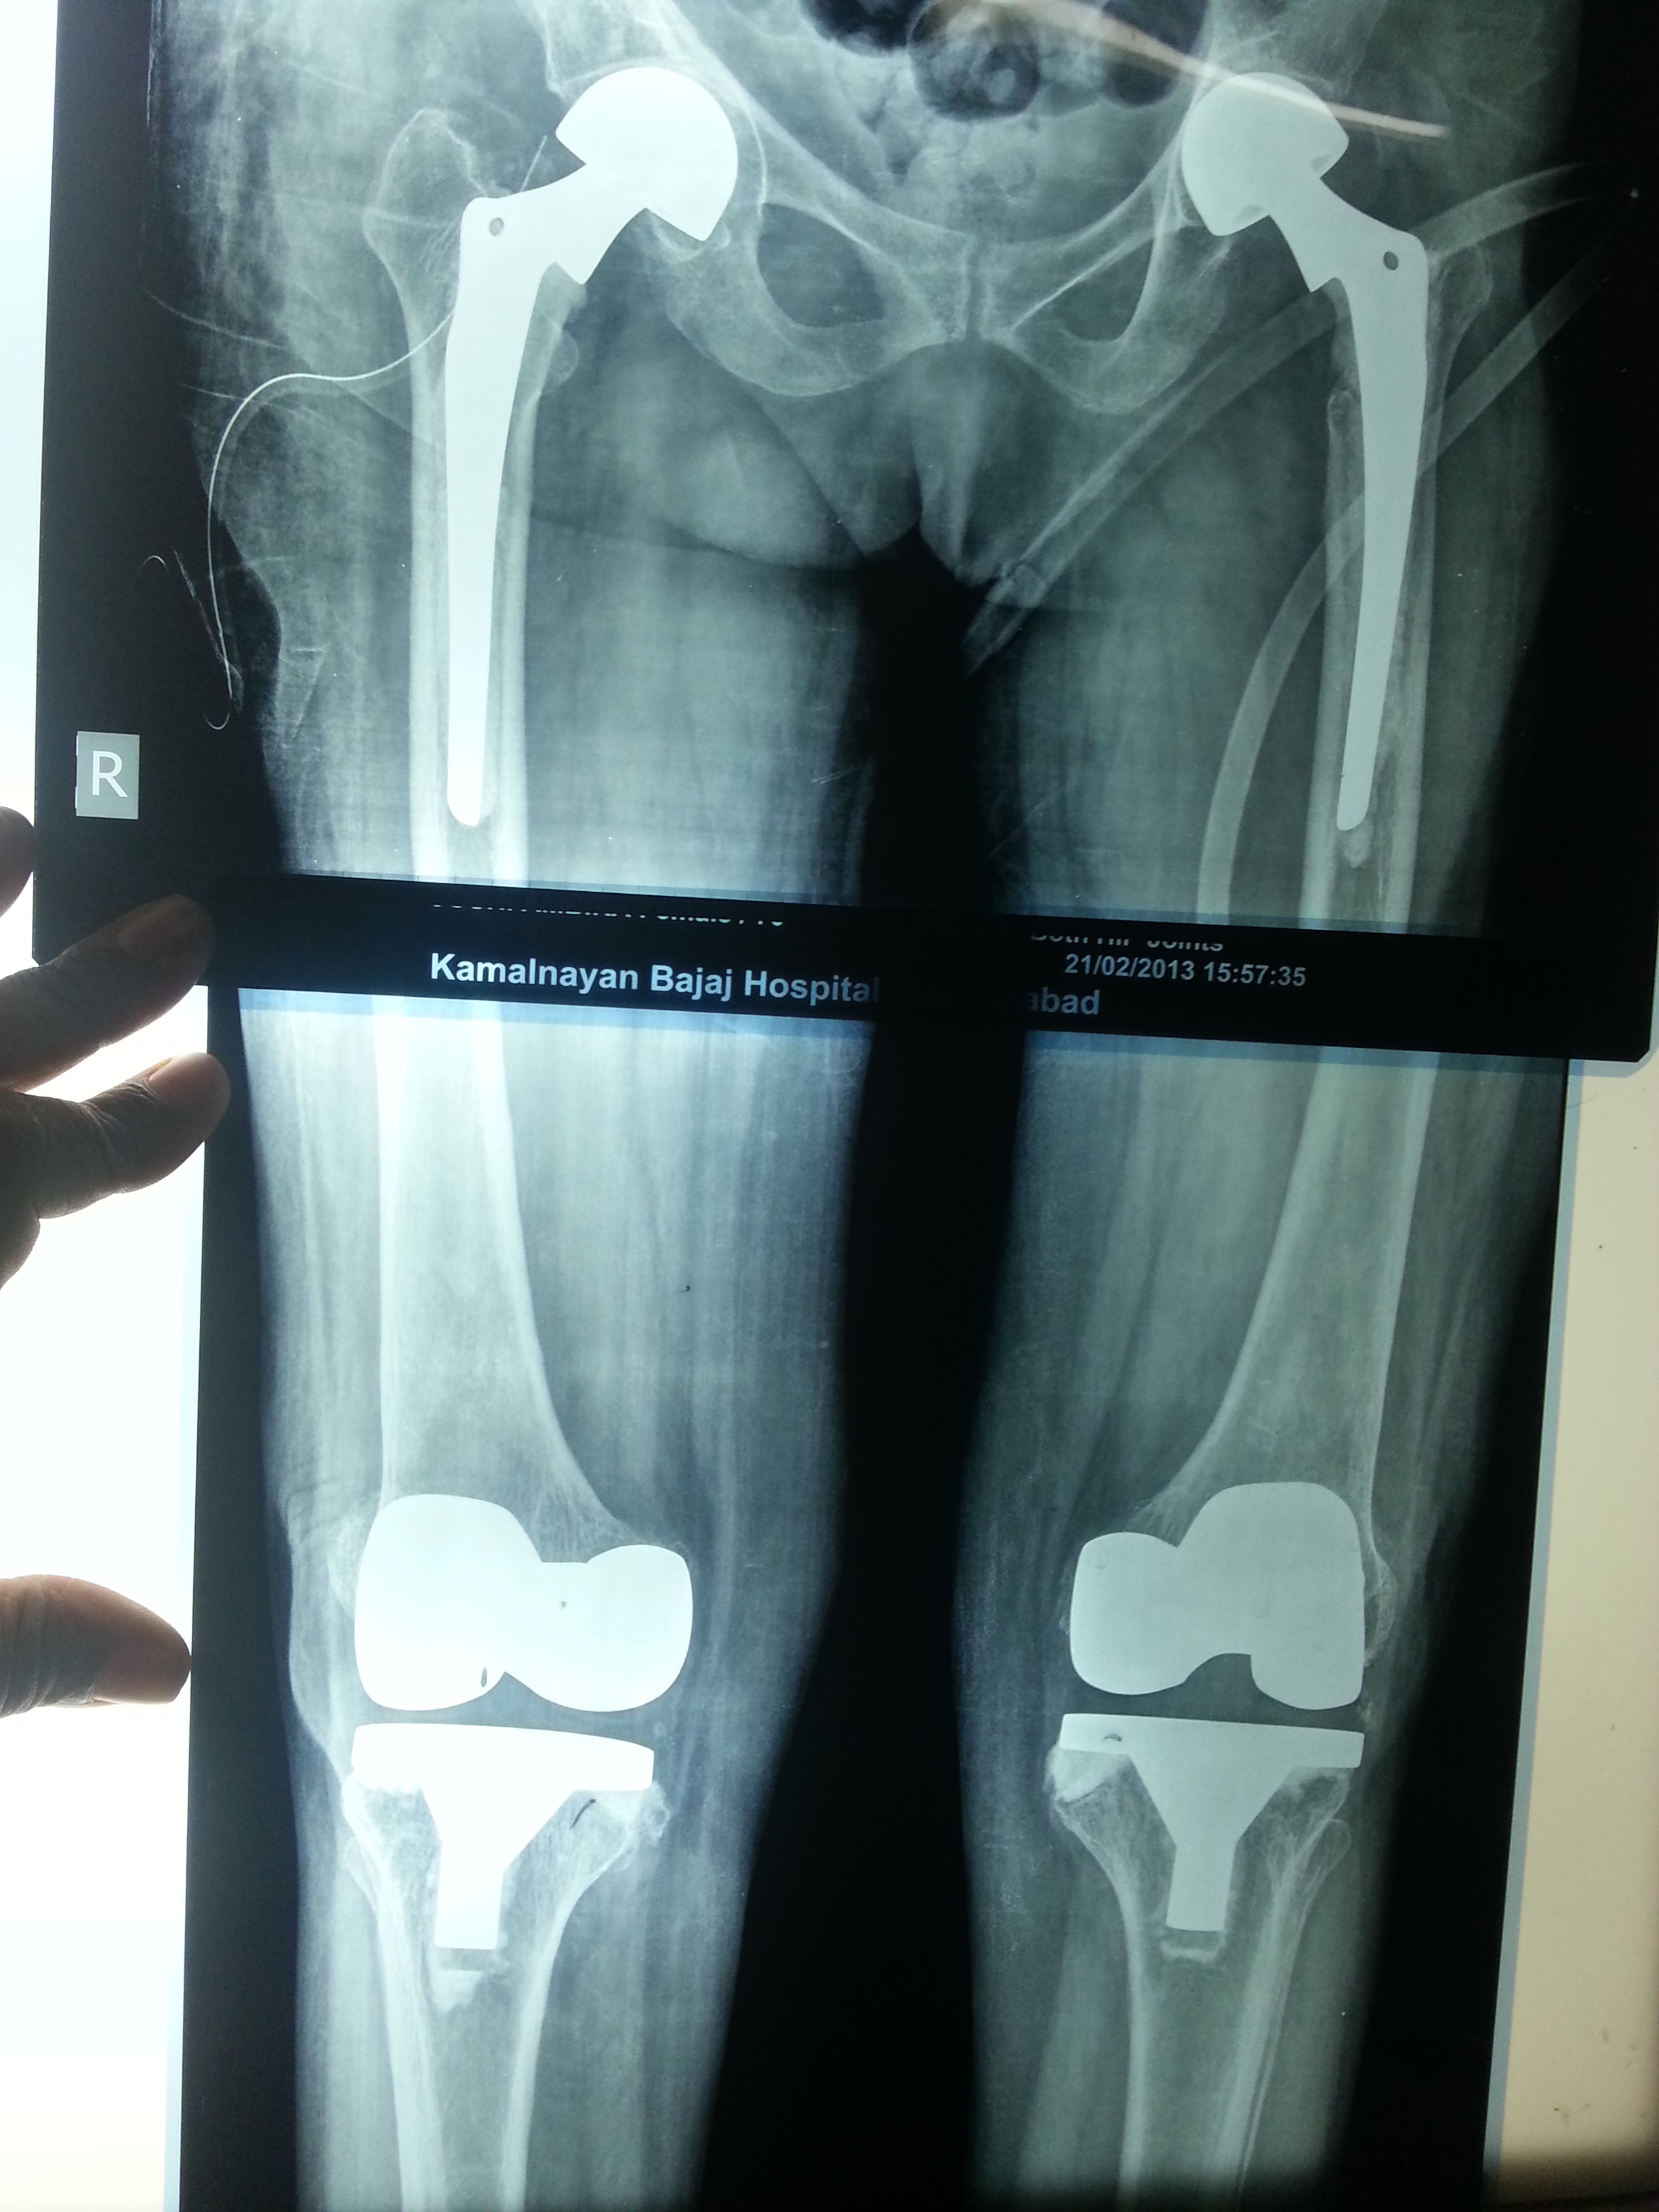

Name:Verified patient

Age: 70

My own uncle. Right side rotating platform knee (Depuy ) done 5 yrs back. Left side all poly Oxinium knee ( Smith & n) done 6 months back.

Though the design philosophy for both the knee is so different, clinical outcome was exactly the same.